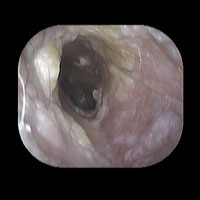

左急性中耳炎(重症)

鼓膜がやや赤くなって腫れています。鼓膜の奥に膿が透けて見えています。抗生剤の内服で鼓膜切開を行わずに22日目で治りました。

7日目